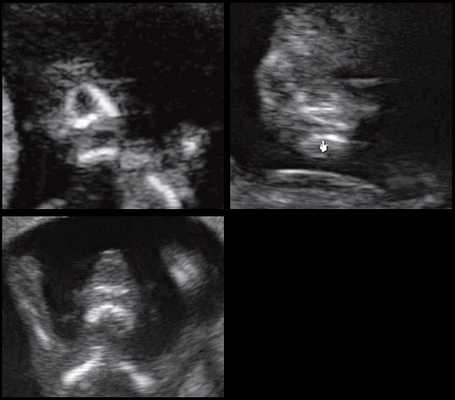

Для качественной оценки особенностей строения нижней челюсти в I триместре беременности специалистами МГО МОНИИАГ совместно с профессором W. Sepulveda (Чили) был изучен и впервые описан новый ультразвуковой признак нижнечелюстной промежуток (mandibular "gap"), визуализируемый при первом скрининговом ("генетическом") ультразвуковом исследовании [18, 19].

Методика базируется на изучении коронарного скана лица плода, так называемого ретроназального треугольника, при котором визуализируется верхняя и нижняя челюсть. Техника получения этого скана чрезвычайно проста и может быть рекомендована для скринингового исследования в 11-14 нед беременности. Эта методика позволяет оценить нижнюю челюсть плода без применения трудоемких оценок, и не сопряжена с математически сложными расчетами коэффициентов, также она существенно не увеличивает время осмотра. Коронарный скан можно оценивать как в режиме 2D, так и в режиме объемной эховизуализации 3D. Методика оценки коронарного скана лица плода в I триместре беременности показана на рисунке 6.

Рис. 6. Методика оценки коронарного скана лица плода в I триместре беременности.

Обе ветви нижней челюсти при сроке 11-14 нед беременности выглядят гиперэхогенными, а в месте слияния имеют характерный гипоэхогенный промежуток, ультразвуковой "разрыв". Этот признак визуализируется при нормальном развитии нижней челюсти (mandibular "gap").

Такие особенности ультразвуковой анатомии связаны с этапами эмбрионального развития костей нижней челюсти, ветви которой начинают развиваться из первой жаберной дуги с 7-й недели эмбрионального развития (рис. 7), и, постепенно приближаясь друг к другу к концу I триместра (на 14-й неделе беременности), образуют синостоз в области подбородка.

Размер этого промежутка уменьшается с увеличением срока беременности. Нижнечелюстной промежуток здорового плода представлен на рисунке 8.

Рис. 8. Нижнечелюстной промежуток в 13 нед беременности при нормальном развитии нижней челюсти.

При патологии нижней челюсти (микрогнатии) в срок 11-14 нед беременности при изучении коронарного скана лица нижнечелюстной "промежуток" отсутствует, нижняя челюсть представлена единой, слившейся костной массой. Отсутствие нижнечелюстного "промежутка" (mandibular "gap") при эхографии в этот срок является маркером гипоплазии нижней челюсти (микрогнатии). Варианты отсутствия нижнечелюстного промежутка при микрогнатии при различных синдромах в срок 11-14 нед беременности представлены на рисунке 9.

Рис. 9. Отсутствие нижнечелюстного промежутка при микрогнатии, при различных синдромах нехромосомного генеза в 11-14 нед беременности.

Оценка описанного признака при проведении пренатальной эхографии I триместра беременности не только проста в методологии и не требует больших затрат по времени исследования, но и высоко информативна, диагностически точна и специфична.